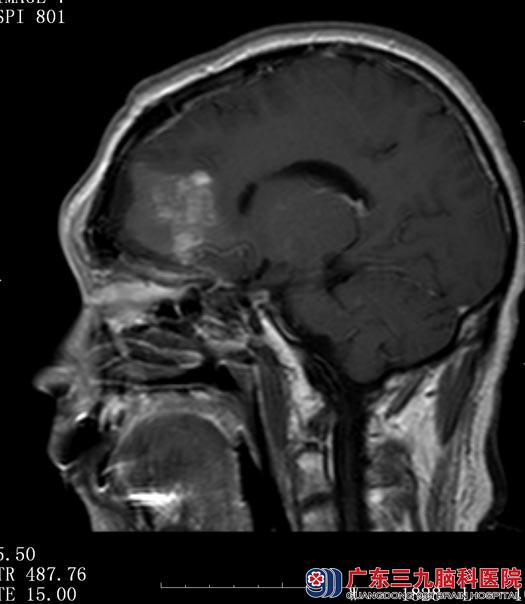

由综合神经外科鲁明主任主刀,在全麻下行前颅窝底脑膜瘤切除术,显微镜下将肿瘤全切,手术顺利。术后王先生自诉困乏感明显好转,现仍在进一步康复中。

▲术后MR